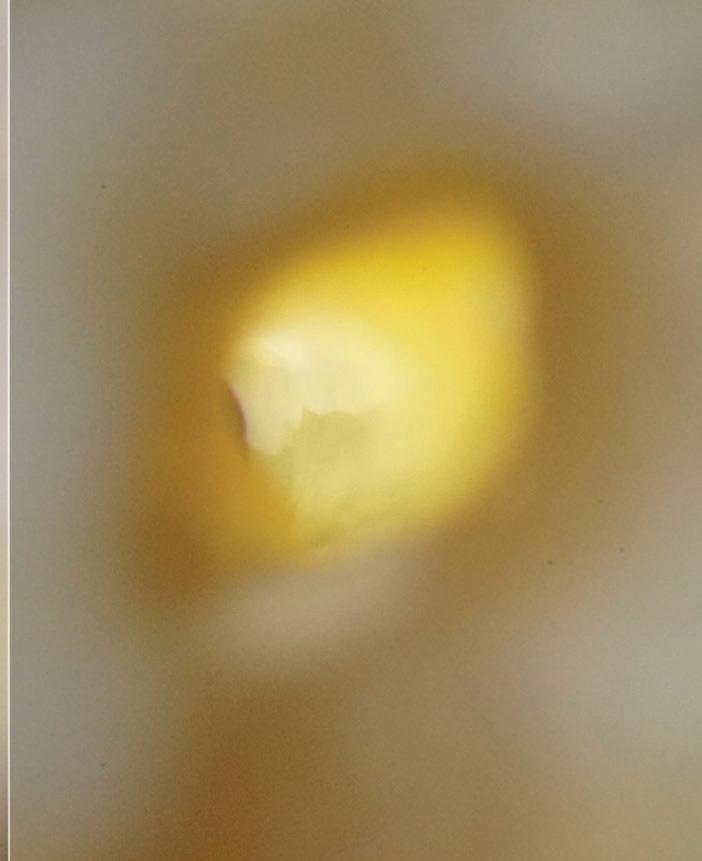

A lesser known risk is extrusion of calcium hydroxide (Ca[OH]2), commonly used as an intracanal medicament. This agent can also result in severe neurovascular injury when extruded into the periapical space. Its high pH (~12.5) can cause protein denaturation, fat necrosis, and chemical injury to nerve tissue.11,12 In a case series reported by Gluskin et al, 5 patients experienced persistent paresthesia and dysesthesia after Ca(OH) 2 was extruded into the inferior alveolar nerve space.13 These injuries were linked to direct chemical damage and potential ischemic necrosis, with radiographic evidence of radiopaque material near the mandibular canal. Beyond localized nerve injury, Ca(OH)2 extrusion can also result in more widespread vascular complications, such as Nicolau syndrome, a rare but severe ischemic event caused by intra-arterial or periarterial injection of irritants.14,15 The literature includes case reports of patients who received Ca(OH)2 injections mistakenly placed near arterial structures and developed cutaneous necrosis, severe tissue ischemia, and in some cases, permanent scarring or functional loss.11,14,15 These findings underscore that even small volumes of Ca(OH)2 can trigger vascular spasm, thrombosis, or embolic events, injuring tissues distant from the site of extrusion (Fig 2).

Fig 2. Calcium hydroxide extrusion. During treatment of the mandibular left first molar, dysesthesia (burning pain) and paresthesia resulted from a substantial overfill of calcium hydroxide into the inferior alveolar nerve canal. (Courtesy of